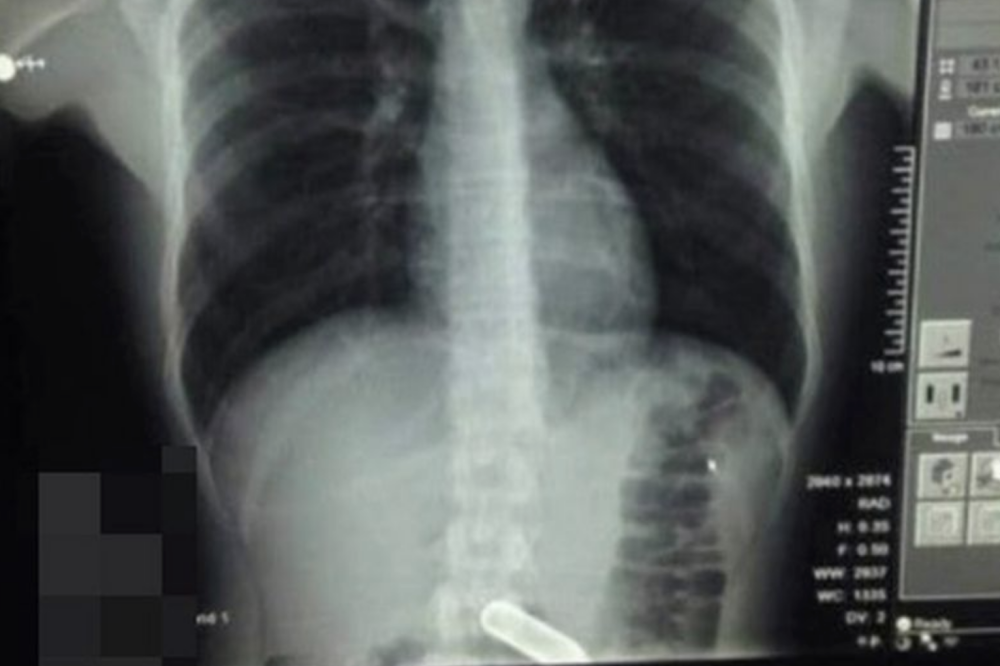

据英国《镜报》2020年7月26日报道 , 7月24日来自英国22岁的约翰·芬森和好朋友在化妆舞会上打赌50英镑(约和人民币453元) , 赌他能不能吞下一个笑气罐子 。 结果约翰一口气咽下了一整个笑气罐 , 他的朋友意识到问题的严重性 , 赶紧说服约翰去了医院 。 医护人员见到如此罕见的情况都很担心 , 怕笑气罐会在约翰的胃里爆炸 。

医生们翻阅了众多的病例 , 只在一头牛的病例里找到了类似的情况 。 大家非常担心如果笑气罐上的金属锭突然在他的胃里爆炸 , 他可能会死在手术台上 。 约翰的主治医生打电话给一位气管专科医生 , 他赶忙来到医院为这名年轻人做了紧急手术 。

【爆炸|英国男孩和同学打赌吞下一个笑气罐,医生担心气罐会在他胃里爆炸】幸运的是 , 这位气管科医生成功地从约翰胃里取出了这只已经被严重腐蚀的笑气罐 , 而没有引发致命的爆炸 。

康复之后的约翰说:“医生一开始担心它会爆炸 , 一旦爆炸我的五脏六腑就都会被炸飞 。 幸运的是 , 外科医生用一个带摄像头的小渔网把它捞了出来 。 ”

约翰说:“在做手术之前 , 我听医生说他们可以参考的唯一病例就是以前有一头牛不小心吞下了同样的东西 。 我现在成为了一个罕见的医学案例被大家研究 。 医生告诉我我的胃可能需要被切开 , 所以当我从病床上苏醒过来时我做的第一件事就是撩起我的衣服看看是否有伤疤 。 ”